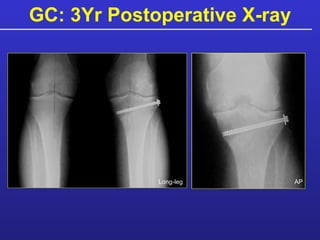

Patient Example: GC 7 o  varus L-knee Medial joint space narrowing Active 53 y.o. male. Meniscectomy: 1986, 1996 Medial meniscus-allograft 3/99  Paste Graft MFC & MTP High medial tibial osteotomy (Bionx wedge and allograft bone)

GC: Postoperative X-Ray Long-leg AP

GC: 3Yr Postoperative X-ray AP Long-leg